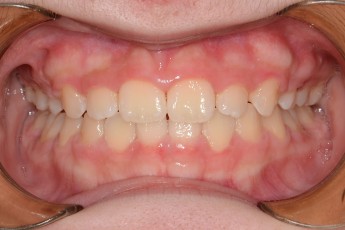

Before

After